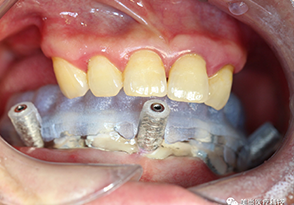

种植导板和临床修复体的制作(3D打印技术)

7.导板设计(分层导板-美尚专利)

9.导板打印完成(专利产品)

10.导板打印完成(专利产品)

11.分层导板有助于口内就位